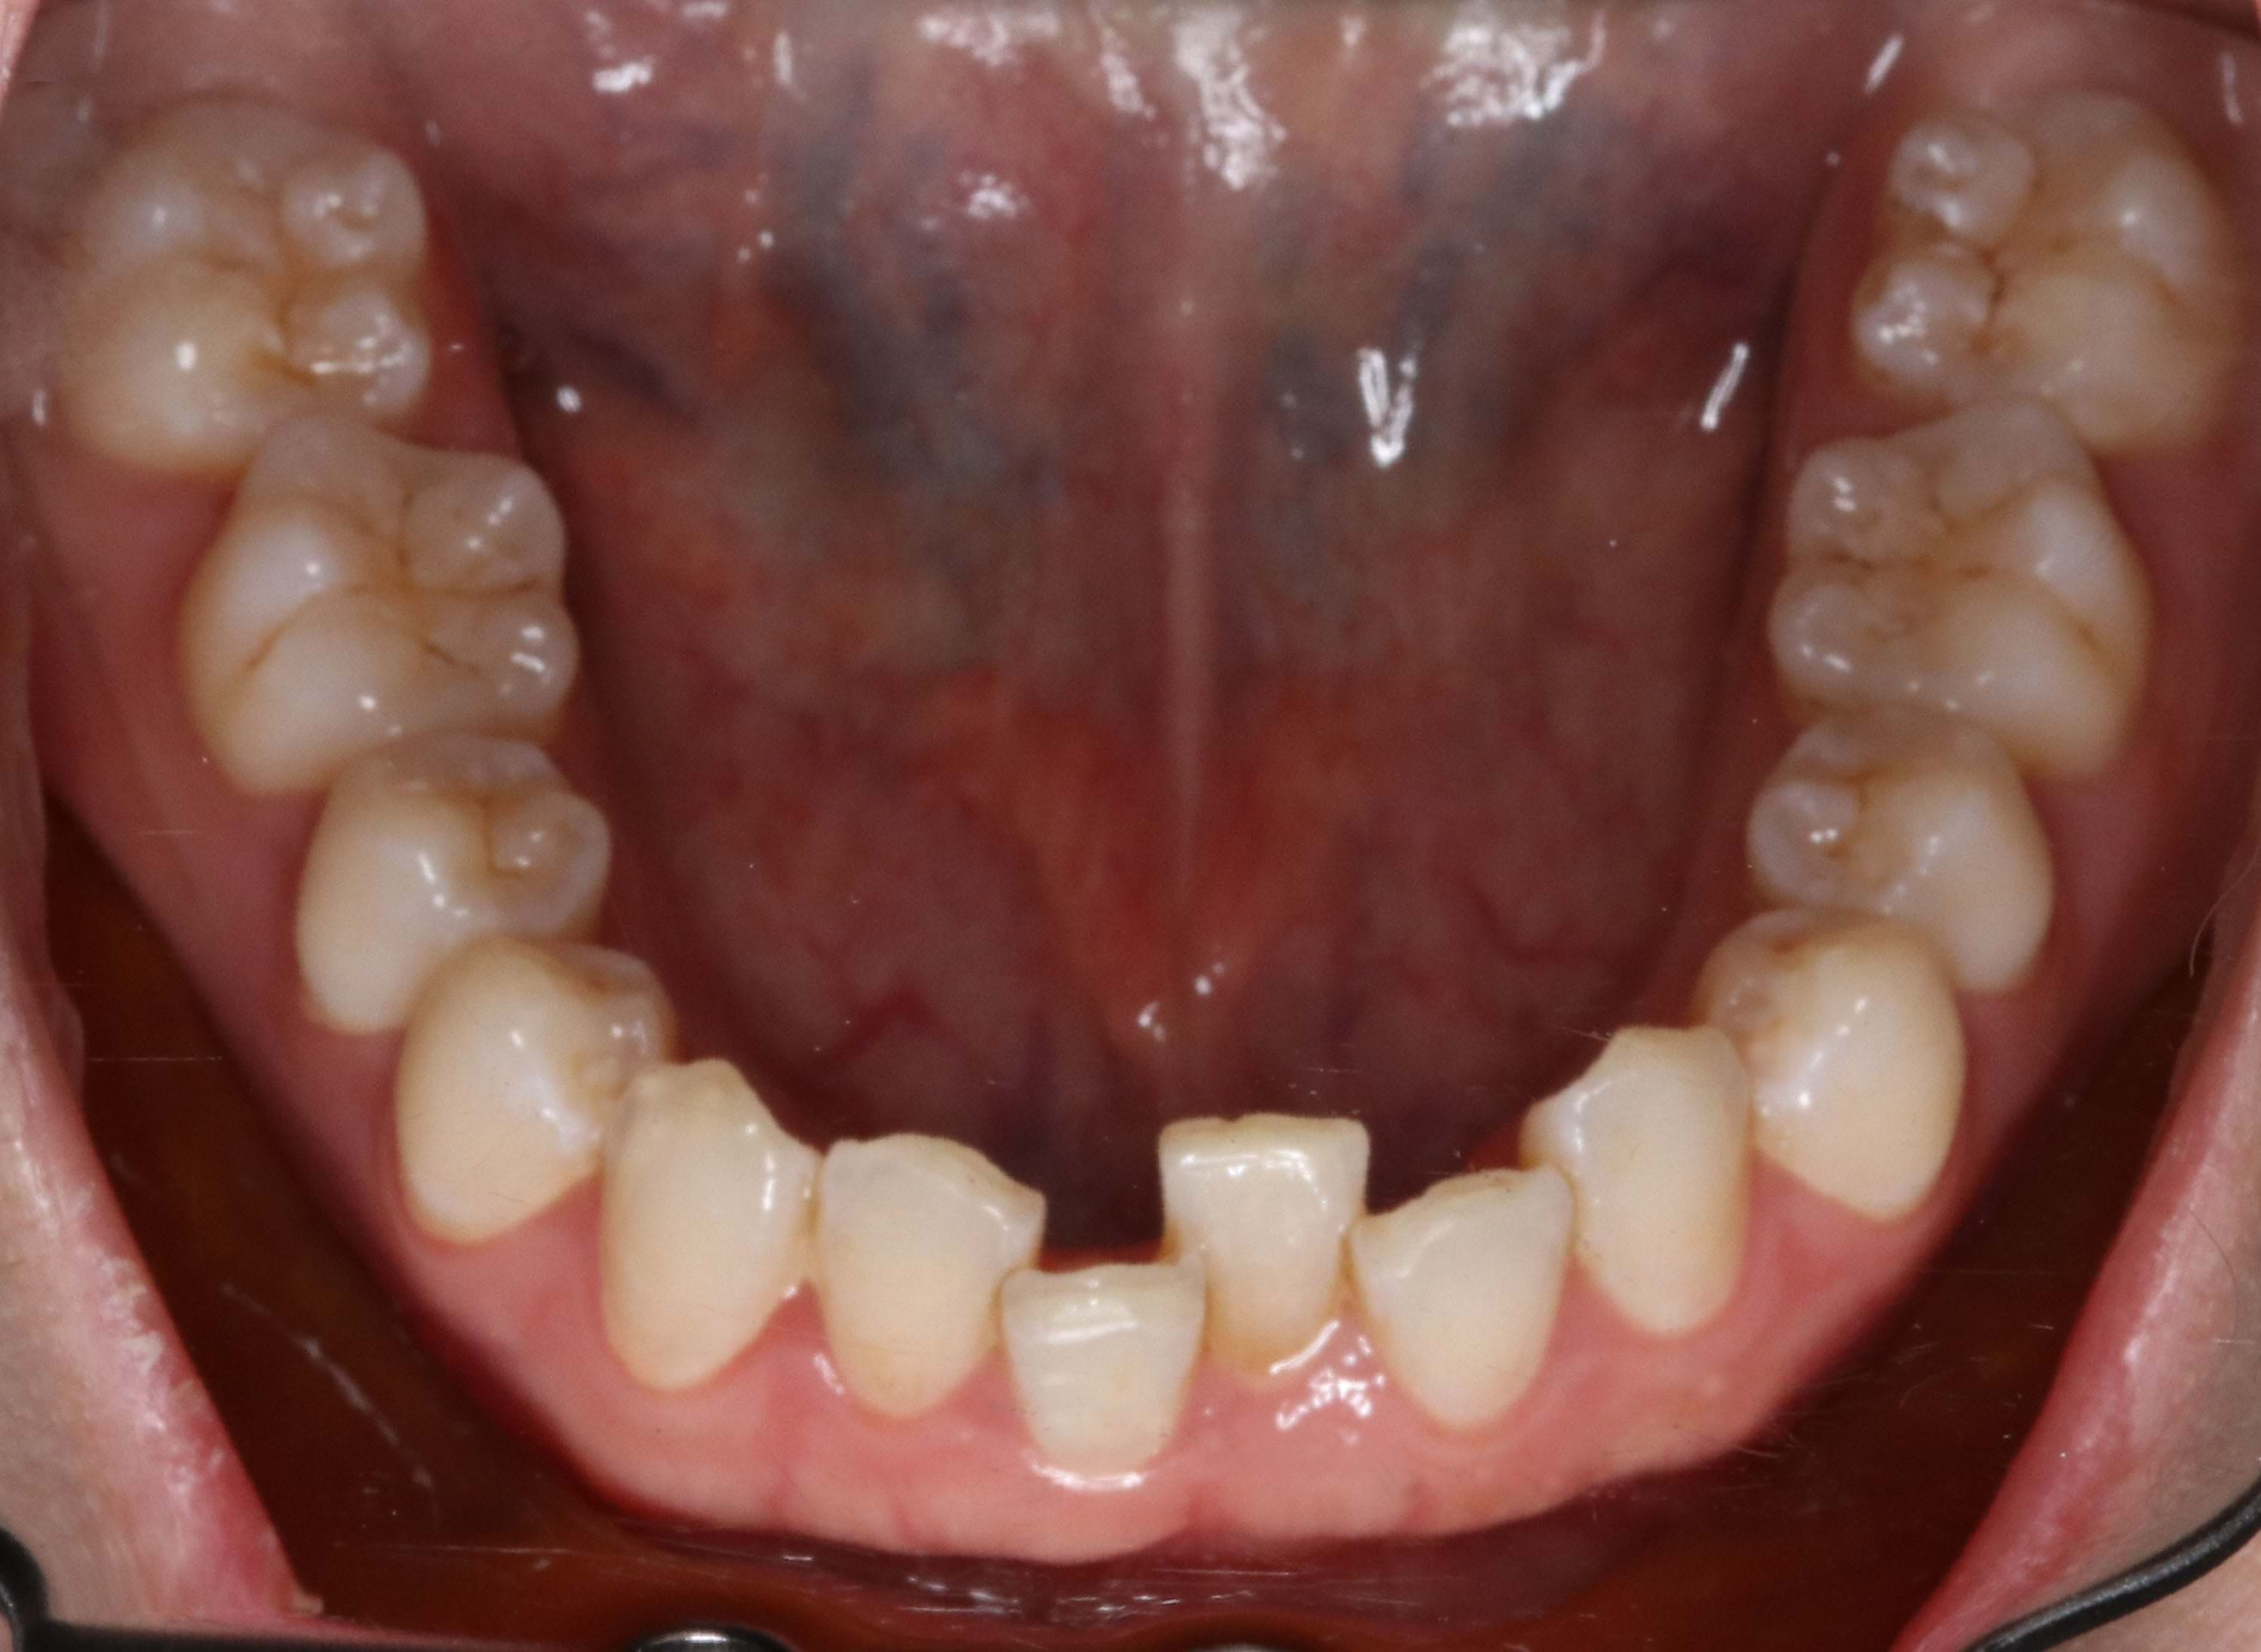

Braces Retainer Relapse . — the unfortunate tale of orthodontic relapse. — retainers ensure your teeth and gums stay in place after removing braces to prevent relapse and reversal of. The most immediate consequence of not wearing a retainer is the relapse of your. — after your braces are removed, you should keep a retainer for at least six months to a year. in the first month after the braces are removed, the risk of relapse is very high. Following that, your orthodontist may advise you to wear the retainer at night for a few years or indefinitely. Neglecting your retainer for an extended period of time can lead to orthodontic relapse. Without retainers, there is a tendency for. — retention and relapse in clinical practice. Sj littlewood, s kandasamy, g huang.

Neglecting your retainer for an extended period of time can lead to orthodontic relapse. Sj littlewood, s kandasamy, g huang. — retainers ensure your teeth and gums stay in place after removing braces to prevent relapse and reversal of. Without retainers, there is a tendency for. in the first month after the braces are removed, the risk of relapse is very high. — after your braces are removed, you should keep a retainer for at least six months to a year. The most immediate consequence of not wearing a retainer is the relapse of your. Following that, your orthodontist may advise you to wear the retainer at night for a few years or indefinitely. — the unfortunate tale of orthodontic relapse. — retention and relapse in clinical practice.

Braces Retainer Relapse — retainers ensure your teeth and gums stay in place after removing braces to prevent relapse and reversal of. Sj littlewood, s kandasamy, g huang. — retention and relapse in clinical practice. — after your braces are removed, you should keep a retainer for at least six months to a year. — the unfortunate tale of orthodontic relapse. — retainers ensure your teeth and gums stay in place after removing braces to prevent relapse and reversal of. Neglecting your retainer for an extended period of time can lead to orthodontic relapse. Following that, your orthodontist may advise you to wear the retainer at night for a few years or indefinitely. in the first month after the braces are removed, the risk of relapse is very high. The most immediate consequence of not wearing a retainer is the relapse of your. Without retainers, there is a tendency for.